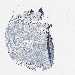

SKIN CANCER - Protein expressioni

A mouse-over function shows sample information and annotation data. Click on an image to view it in a full screen mode. Samples can be filtered based on level of antibody staining by selecting one or several of the following categories: high, medium, low and not detected. The assay and annotation is described here.

Note that samples used for immunohistochemistry by the Human Protein Atlas do not correspond to samples in the TCGA dataset.

Antibody stainingi

Antibody staining in the annotated cell types in the current human tissue is reported as not detected, low, medium, or high, based on conventional immunohistochemistry profiling in selected tissues. This score is based on the combination of the staining intensity and fraction of stained cells.

Each image is clickable and will lead to virtual microscopy that enables deeper exploration of all samples and also displays staining intensity scores, fraction scores and subcellular localization as well as patient and tissue information for each sample.

Antibody HPA015786

Staining

Squamous cell carcinoma, NOS